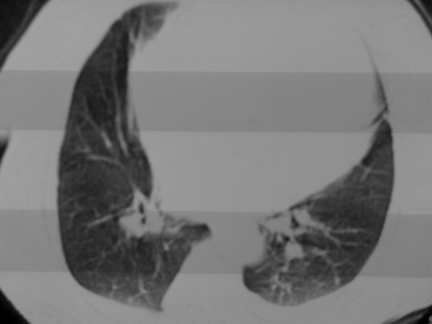

标题: CT13142:女 80 胸闷、气短、1w [打印本页]

标题: CT13142:女 80 胸闷、气短、1w

右肺炎性变,双侧甲状腺肿,胸膜肥厚。

右肺炎性变

双侧胸腔积液

缩窄性心包炎

左室为主的心脏增大。

胸膜肥厚,

气管,支气管软骨钙化。

右肺感染;双侧胸腔少量积液,心影增大,可能与心功不全有关;胸内甲状腺肿。

右肺炎性变,双侧甲状腺肿,胸膜肥厚,心影增大考虑心功能不全.

胸内甲状腺肿;右肺感染;双侧胸腔少量积液。

胸内甲状腺肿;右肺中叶感染;双侧胸腔少量积液;心影增大,考虑有心功能不全。